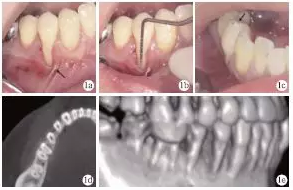

臨床檢查發現,患者全口牙齦無明顯紅腫,探診深度1~4mm,BOP(+)<15%;#44頰側牙頸部充填物,頰側可見9mm齦退縮,超過膜齦聯合,僅存小于1mm的角化齦,且近中見系帶附著,近遠中齦乳頭均存在輕度退縮(圖1a、1b);正中咬合時可捫及#44功能性動度,頰尖舌斜面可見咬合高點(圖1c)。術前CT見#44頰側牙槽骨吸收達根尖1/3,鄰面擴展達根間區,鄰面牙槽骨高度降低(圖1d、1e)。根據臨床檢查和CT檢查,診斷為#44Miller Ⅲ°牙齦退縮。

圖1 術前臨床及X線檢查